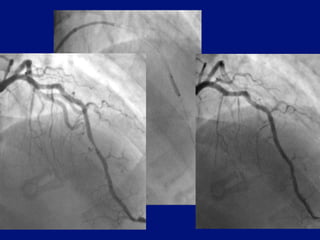

Balloon / stent delivery CTO

CCI in press 2010 Mamas Ordoubadi Fraser

More difficult stent delivery

Extension crosses tortuousity

easier than stent

Pull catheter in over balloon inflated

distal lesion

Pulling is less traumatic than pushing

Wire re-centered

Conventional anchor

Balloon / stentdelivery CTO CCI in press 2010 Mamas Ordoubadi Fraser

Pull catheter inover balloon inflated distal lesion

Pulling is lesstraumatic than pushing Wire re-centered